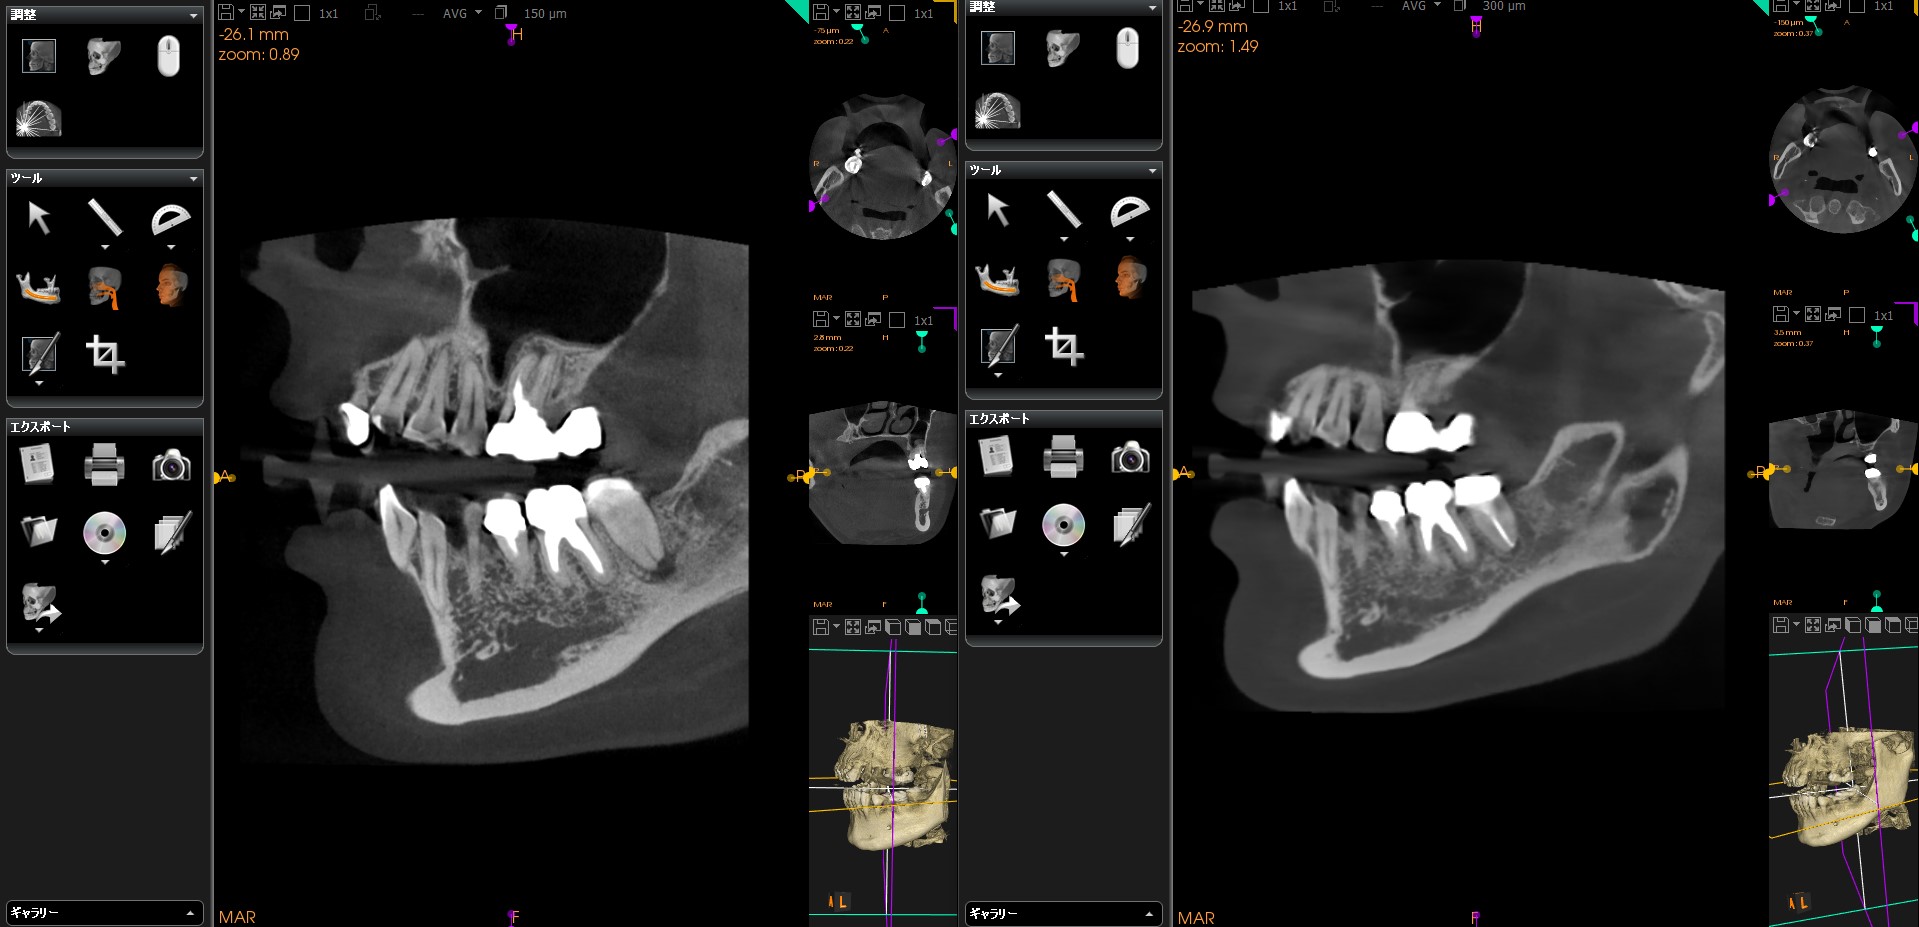

そしてこちらが処置前と処置後のCTになります🦷✨!!!

このように根管治療を精密に行うことにより根の先の膿は消え歯牙保存へと繋がります